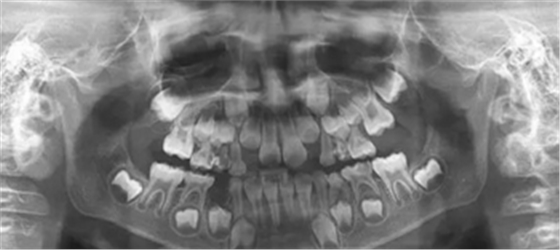

3、曲面斷層片 示恒牙萌出間隙不足